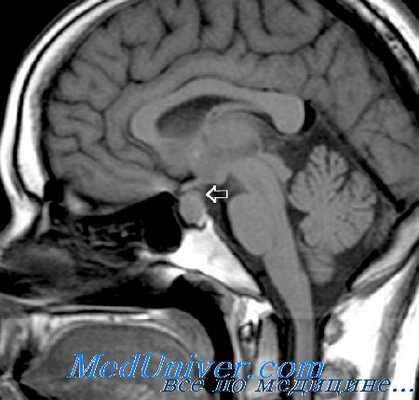

Нейровизуализацию опухоли гипофиза позволяет осуществить рентгенография черепа и зоны турецкого седла, МРТ и КТ головного мозга. Рентгенологически могут определяться увеличение размеров турецкого седла и эрозия его дна, а также увеличение нижней челюсти и пазух носа, утолщение костей черепа, и расширение межзубных промежутков. С помощью МРТ головного мозга возможно увидеть опухоли гипофиза диаметром менее 5 мм. Компьютерная томография подтверждает наличие аденомы и ее точные размеры.

С целью визуализации аденомы проводят рентгенографию турецкого седла, которая выявляет костные признаки: остеопороз с разрушением спинки турецкого седла, типичную двуконтурность его дна. Дополнительно используют пневмоцистернографию, которая определяет смещение хиазмальных цистерн от их нормального положения.

Более точные данные могут быть получены в ходе КТ черепа и МРТ головного мозга, КТ турецкого седла. Однако около 25-35% аденом гипофиза имеют настолько малый размер, что их визуализация не удается даже при современных возможностях томографии. Если есть основания считать, что аденома гипофиза растет в сторону кавернозного синуса, назначают проведение ангиографии головного мозга.

Высокоинформативным методом при подозрении на пролактиному является МРТ головного мозга с прицельным исследованием гипофиза контрастирующим веществом гадолиниумом. Магнитно-резонансное сканирование позволяет выявить очертания небольших аденом, их интраселлярное или экстраселлярное расположение, а также опухоли, расположенные в мягкотканных образованиях (кавернозном синусе, в области сонных артерий и т д.).

При макропролактиномах более применимо КТ головного мозга, т. к. хорошо визуализирует костные структуры (основание турецкого седла – анатомическую область расположения гипофиза).